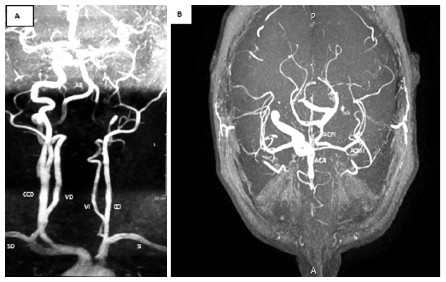

Se decidió realizar una angioresonancia magnética con gadolinio de aorta ascendente, cayado y vasos supra aórticos e intracraneales, para confirmar el diagnóstico y descartar patología asociada (Figura 2). Este estudio confirmó lo observado en el ultrasonido, descartó la presencia de aneurismas en vasos intracraneanos, los cuales se describen con una prevalencia del 25 al 35%, cifra muy superior al 2 al 4% reportado en la población general. (2) El estudio demostró una circulación colateral de tipo fetal, en la que la arteria cerebral anterior del hemisferio afectado recibe aporte de flujo sanguíneo de la arteria carótida interna contralateral, a través de la arteria comunicante anterior, mientras que la arteria cerebral media se nutre desde la arteria basilar homolateral por medio de una arteria comunicante posterior de buen desarrollo. Éste, es el tipo de circulación colateral más prevalente (alrededor del 70% de los casos) en ausencia de arteria carótida interna. (3) Los otros dos son, el tipo adulto en el que la arteria carótida interna contralateral suple, a través de la arteria comunicante anterior, tanto a la arteria cerebral anterior como a la cerebral media del lado afectado. Por último, existe un tercer patrón, en el cual, el hemisferio que padece la agenesia de carótida interna recibe flujo de anastomosis anómalas: a) desde la arteria carótida externa por intermedio de la arteria maxilar, oftálmica, vidiana o meníngeas accesorias, b) desde la porción cavernosa de la arteria carótida interna contralateral por conexiones transelares intracavernosas, o c) mediante vasos embrionarios persistentes.

Panel A. Cayado Aórtico. El primer vaso que emerge en el cayado aórtico, es el tronco braquiocefálico derecho (TBD), de éste se originan la arteria carótida común (CCD) y subclavia derecha (SD), de esta última sale la arteria vertebral derecha (VD) que junto con la contralateral de menor desarrollo (VI), forman la arteria basilar (AB). Luego, se ve el origen de una arteria carótida común izquierda hipoplásica (CCI). La vertebral izquierda tiene su origen en la subclavia izquierda (SI). Panel B. Vasos intracraneaneos. En el hemisferio izquierdo, en ausencia de arteria carótida interna, la arteria cerebral anterior izquierda (ACAI) se nutre del sistema carotideo contralateral, y la arteria cerebral media (ACMI) del sistema basilar homolateral mediante una arteria comunicante posterior hipertrófica (ACPI). Circulación colateral del “tipo fetal”.